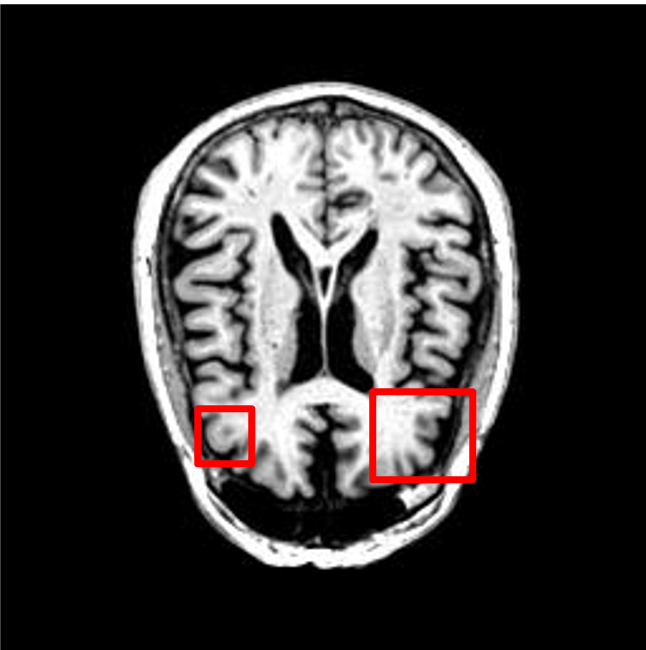

We present the results of conditional medical image generation with and without our proposed method LD, in Tab. 1, and Fig. 5. In Fig. 4, we show examples of brain MR images generated by the different methods combined with LD for two different classes of cognitively normal (CN) and Alzheimer’s disease (AD). The results were obtained by fine-tuning the corresponding method on the medical data with LD. As shown in Fig. 4, the samples generated through Custom Diffusion tuning are realistically looking while understanding the difference between CN and AD brain properly, which other methods failed at. Textual inversion seems to understand the concept but fails to understand the brain structure properly. Quantitative results on the performance of all our methods are presented in Tab. 1. Qualitative results on the CheXpert [19] dataset, along with a user study and ablation of different parameters, optimization algorithm, and more, are included in the supplementary material.

Qualitatively, Fig. 5 shows a significant improvement of the visual realism across all methods when using a drift of . The background is consistently black as in real brain MR images; the shape of the brain becomes more realistic, and the white and gray matter structure improves. For an analytical evaluation, we calculated the FID between our test data and 200 synthetically generated images from each method (100 CN, 100 AD). The results in Tab. 1 demonstrate that LD improves the ability of the model to generate realistic MRI slices for both healthy brains and brains with Alzheimer’s disease. For this reason, all following experiments were done with LD.

![[Uncaptioned image]](extracted/6101136/images/instructpix2pix/source1_box.png)

![[Uncaptioned image]](extracted/6101136/images/instructpix2pix/target1_box.png)

![[Uncaptioned image]](extracted/6101136/images/instructpix2pix/results1_box.png)

![[Uncaptioned image]](extracted/6101136/images/instructpix2pix/source2_box.png)

![[Uncaptioned image]](extracted/6101136/images/instructpix2pix/target2_box.png)

![[Uncaptioned image]](extracted/6101136/images/instructpix2pix/results2_box.png)